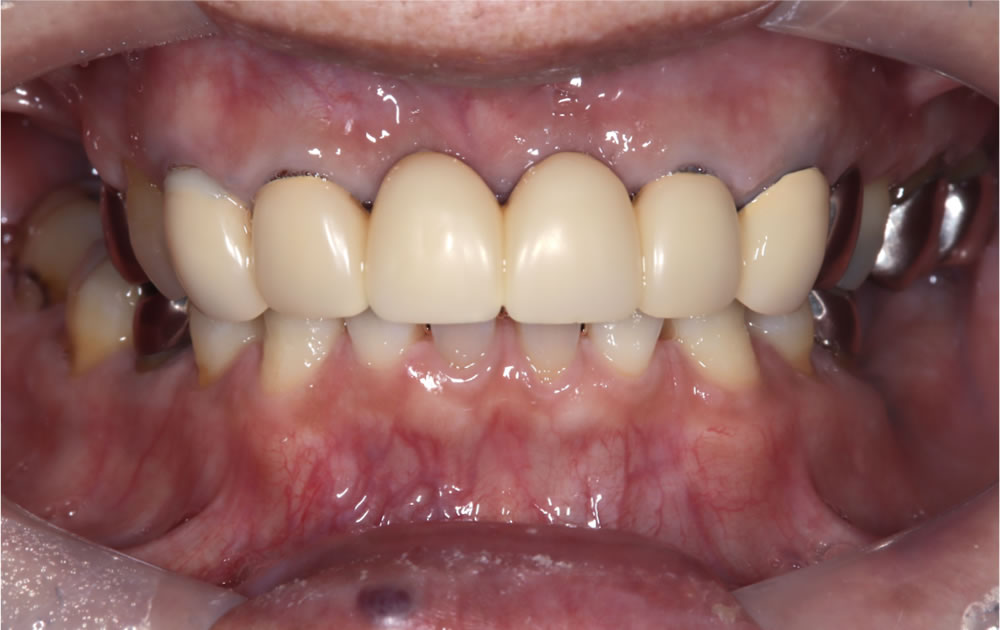

完成した最終的な上部構造(人工歯)

採取した型を基に制作した最終的な上部構造(人工歯)です。

治療完了

最終的な上部構造(人工歯)を口腔内に装着し、咬み合わせを調整して治療完了となりました。